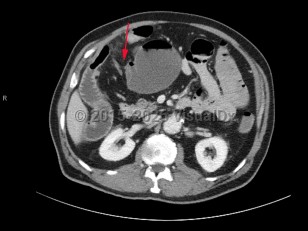

Neutropenic enterocolitisNeutropenic enterocolitis

Intussusception